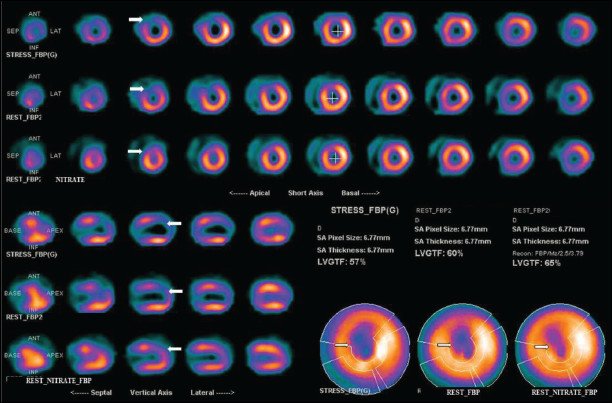

Myocardial Perfusion Imaging (MPI) is a non-invasive procedure utilized to assess significant coronary artery disease (CAD). This diagnostic and prognostic examination determines the extent and location of impaired blood flow to the heart, as well as evaluates pumping function and the presence of scarred heart tissue. A small amount of radiotracer is injected intravenously during both resting and stress states, achieved through physical exertion (such as treadmill exercise) or pharmacological stress. Throughout the procedure, blood pressure and electrocardiogram monitoring are conducted. Healthy heart muscle, receiving adequate blood flow, will accumulate more of the radiotracer compared to regions supplied by diseased coronary arteries.

Blood flow to the heart at rest and during stress

Left ventricular pumping function, including ejection fraction, wall motion, and wall thickening

Offering enhanced diagnostic precision compared to standard stress tests, abnormal perfusion scans strongly indicate coronary artery disease (CAD). MPI plays a crucial role in determining whether patients should undergo angiograms, angioplasty, bypass surgery, or medical management. It’s also instrumental in monitoring the effectiveness of these treatment approaches.MPI and coronary angiography (conventional or CT) provide complementary yet distinct information for diagnosing and evaluating CAD. While coronary angiography detects atherosclerosis, MPI assesses ischemia’s hemodynamic significance, guiding further therapeutic strategies. Notably, patients with angiographically confirmed CAD but negative MPI results exhibit similarly low event rates.

MPI stands as the most prevalent nuclear imaging study in the US, with approximately 10 million procedures conducted annually. It’s deemed the preferred test for evaluating intermediate-risk CAD patients before considering angiography, endorsed by esteemed societies like the American College of Cardiology Foundation, American Society of Nuclear Cardiology, American Heart Association, and others.At NewMedd Diagnostics, we utilize a dual-head gamma camera for rapid acquisition, ensuring patient comfort and minimizing motion artifacts. Advanced software tools like xeleris and Emory Cardiac ToolBox enable us to obtain three-dimensional heart images, depicting stress and resting blood flow. Quantitative parametric assessment and scoring enhance interpretation accuracy.